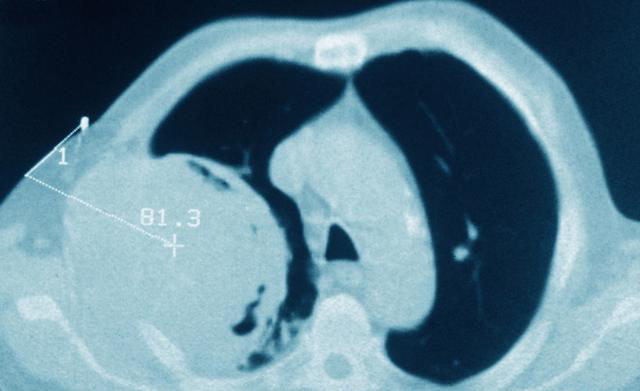

记得还是我刚上班时候的事情,当时是住院医生,接诊了一位患者,身体已经极度虚弱,问病史才知道,当地医生没有条件给他做肺穿刺,气管镜,家属又着急,最终靠CT给他确诊了肺癌,化疗放疗做了一整套,结果最终诊断是肺部淋巴瘤。病理诊断是恶性肿瘤确诊的金标准,没有病理诊断,就不能百分百确定是肺癌,即便CT等影像学检查可以判断是肺部恶性肿瘤,但没有病理诊断,就只能说是肺占位,肺癌可能性大。如果没有病理诊断,不仅不能做放化疗,连门诊特殊病种(门特)申请都无法通过。

为何肺癌确诊必须要病理?1.CT上提示肺癌不一定就是肺癌肺癌虽然是最常见的恶性肿瘤,发病率和死亡率都排第一,但不能单纯从CT上武断的判断一定是肺癌。因为也有不少其他类型疾病,从影像学上看与肺癌极其相似,比如肺炎性假瘤、肺曲霉菌病、肺癌肉瘤等等,这些都是在临床上遇到过的。去年在门诊接诊过两个术后来复查的病人,这两个病人都是因“肺部肿块”行手术治疗,术后病理一个是肺炎性假瘤,另一个是肺曲霉菌。此外,还有一些少见的肺恶性肿瘤,CT上与肺癌难以鉴别,比如肺淋巴瘤、肺肉瘤、肺癌肉瘤、肺类癌等等,这些类型肿瘤与肺癌的治疗方式完全不同。所以,肺癌诊断必须要有组织活检,显微镜下看病理切片才能百分百做出诊断。

总之,没有病理诊断,不能百分百确定是肺癌,更不可能知道是哪种类型。明确的病理诊断是制定放化疗方案的前提条件。当CT高度疑似肺癌的时候,根据患者病情和身体状况,能手术者尽量手术。如果病人年龄较大,体质差,心肺功能不全,不能进行手术的话,根据病灶位置,可以采用支气管镜取活检,也可以进行肺穿刺取活检。